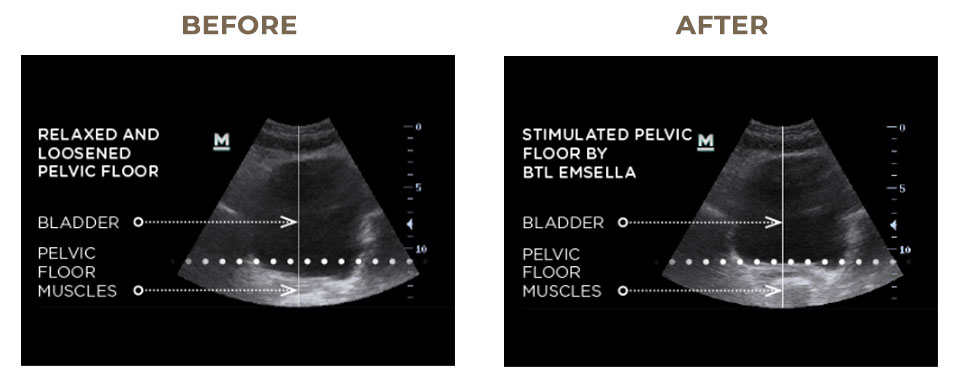

EMSELLA makes strengthening your pelvic floor effortless. During each session, you simply sit, fully clothed,while gentle electromagnetic energy does the work for you. Using advanced HIFEM® technology, EMSELLA stimulates thousands of deep, Kegel-like contractions in just one visit—far more than you could ever achieve on your own.

These focused contractions help re-educate and strengthen weak pelvic floor muscles, restoring healthy control and support for the bladder and surrounding organs. Over time, many clients notice improved confidence, reduced urinary incontinence, and a renewed sense of strength—all without effort, surgery, or downtime.